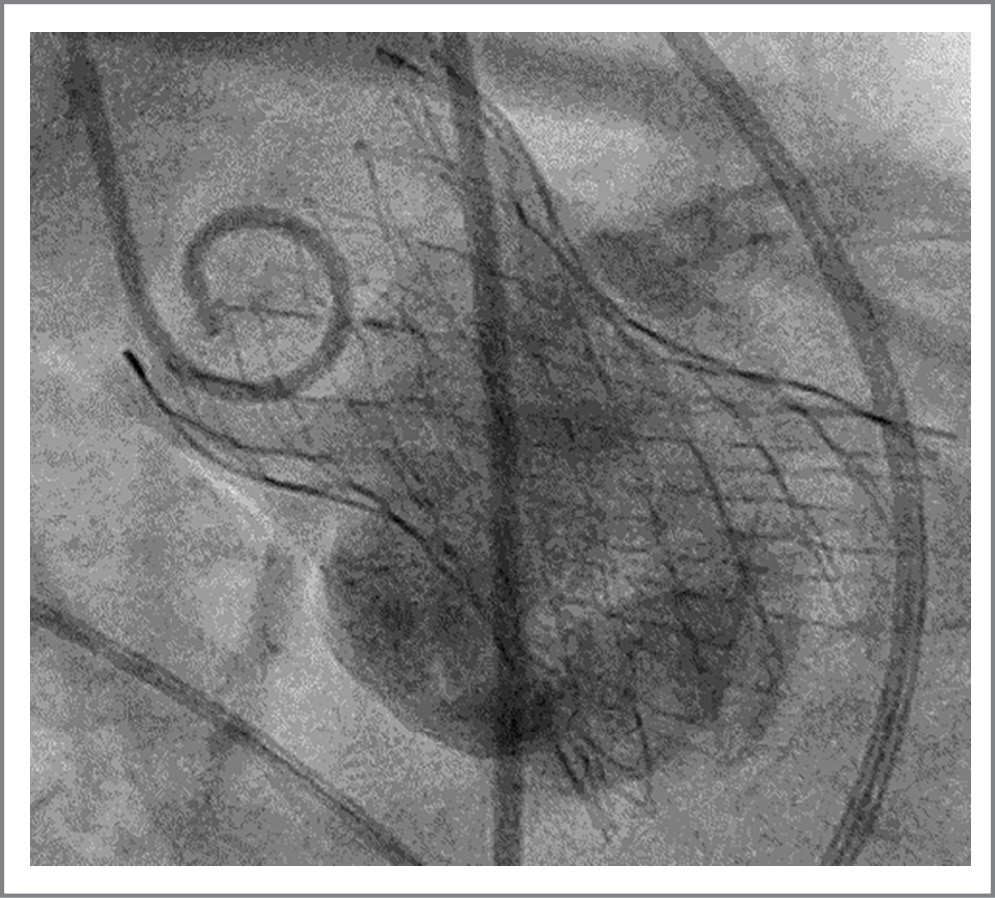

14.02.2019 выполнена транскатетерная имплантация АК биопротезом СoreValve Evolute® 34 мм. Под эндотрахеальным наркозом выполнен доступ к правой бедренной артерии, а затем левой бедренной артерии, установлены интродьюсеры 6F. Через интродьюсер в левой бедренной артерии в корень аорты заведен диагностический катетер pigtail и выполнена диагностическая аортография. Через интродьюсер правой общей бедренной артерии в ЛЖ проведен жесткий проводник с диагностическим катетером. На супержестком проводнике в аортальную позицию подведен баллонный катетер. Выполнена баллонная предилатация АК. По супержесткому проводнику с помощью системы доставки в позицию АК доставлен и имплантирован биологический протез СoreValve Evolute® 34 мм. Проведены постдилатация протеза АК баллоном NUMED 28 мм и контрольная ангиография: коронарные артерии проходимы, запирательная функция клапана осуществляется в полном объеме (рис. 5).

Рис. 5. Финальная интраоперационная аортография. В аортальной позиции установлен самораскрывающийся протез АК.

Fig. 5. Final intraoperative aortography. A self-expanding aortic valve prosthesis is installed in the aortic position.